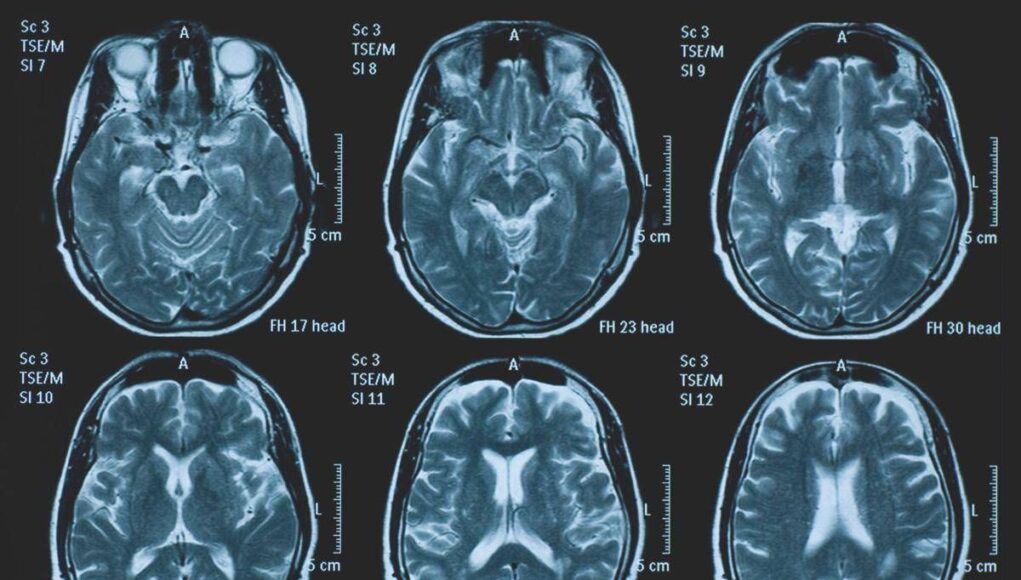

(Adnkronos) – La Commissione europea (Ce) ha autorizzato la commercializzazione condizionata di tovorafenib come monoterapia per il trattamento dei pazienti di etĂ pari o superiore a 6 mesi con glioma pediatrico di basso grado che presentano una fusione o un riarrangiamento del gene Braf o una mutazione Braf-V600, in progressione di malattia dopo una o piĂą terapie sistemiche precedenti. Lo annuncia Ipsen, in una nota, precisando che si tratta della “prima terapia mirata” per questa patologia e che la decisione della Ce si riferisce ai 27 Stati membri della Ue, oltre a Islanda, Liechtenstein e Norvegia. Ogni anno in Ue vengono diagnosticati piĂą di 800 nuovi casi di glioma pediatrico di basso grado (pLgg) con alterazione di Braf. Questo tumore cerebrale, nonostante sia classificato di basso grado (a lenta progressione), comporta un carico significativo e permanente che accompagna la persona per tutta la vita, causando spesso importanti compromissioni fisiche e neurologiche, tra cui perdita della vista, difficoltĂ di linguaggio e disfunzioni motorie, che possono incidere in modo significativo sull’istruzione, l’autonomia e la qualitĂ di vita a lungo termine del bambino. Finora, molti bambini con pLgg hanno dovuto sottoporsi a interventi chirurgici invasivi, a piĂą cicli di chemioterapia e a radioterapia, con conseguenti complicazioni della salute.Â

L’approvazione della Ce si basa sui dati dello studio di fase 2 Firefly-1 che ha valutato tovorafenib in 137 bambini e giovani adulti con pLgg recidivato o refrattario con alterazioni di Braf che avevano ricevuto almeno una precedente terapia sistemica. Nel dettaglio, lo studio ha dimostrato una risposta tumorale clinicamente significativa con un tasso di risposta globale del 71% secondo i criteri Rano-Hgg (ResponseAssessment in Neuro-Oncology criteria for High-Grade Gliomas) e del 53% secondo i criteri Raono-Lgg (Response Assessment in Paediatric Neuro-Oncology for Low-Grade Glioma), con un tasso di beneficio clinico del 77% secondo i criteri Rano-Hgg e del 58% secondo i criteri Rapno-Lgg. Le risposte – riferisce la nota – sono state rapide e durature: sulla base dei criteri Rapno-Lgg, tra coloro che hanno risposto, il tempo mediano alla risposta è stato di 5,4 mesi con una durata mediana della risposta di 18 mesi.Â